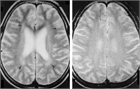

1. 依存の脳内の生物学的基盤についてはこれまでに色々な角度から解析されてきた。現在では脳内の報酬系に関与するドパミン神経系機能が最も注目を浴びている。ドパミン系と、他のオピオイド系、GABA系、グルタミン酸神経系などとの相互作用により依存が形成されるとする理論が提唱されている。